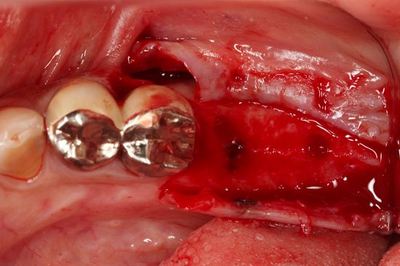

実際のおくちのミラー像です。

過去の金属治療によるメタルタトゥーがありますので

今回のオペ時に除去します。

となりの金属の連結冠も今後除去します。